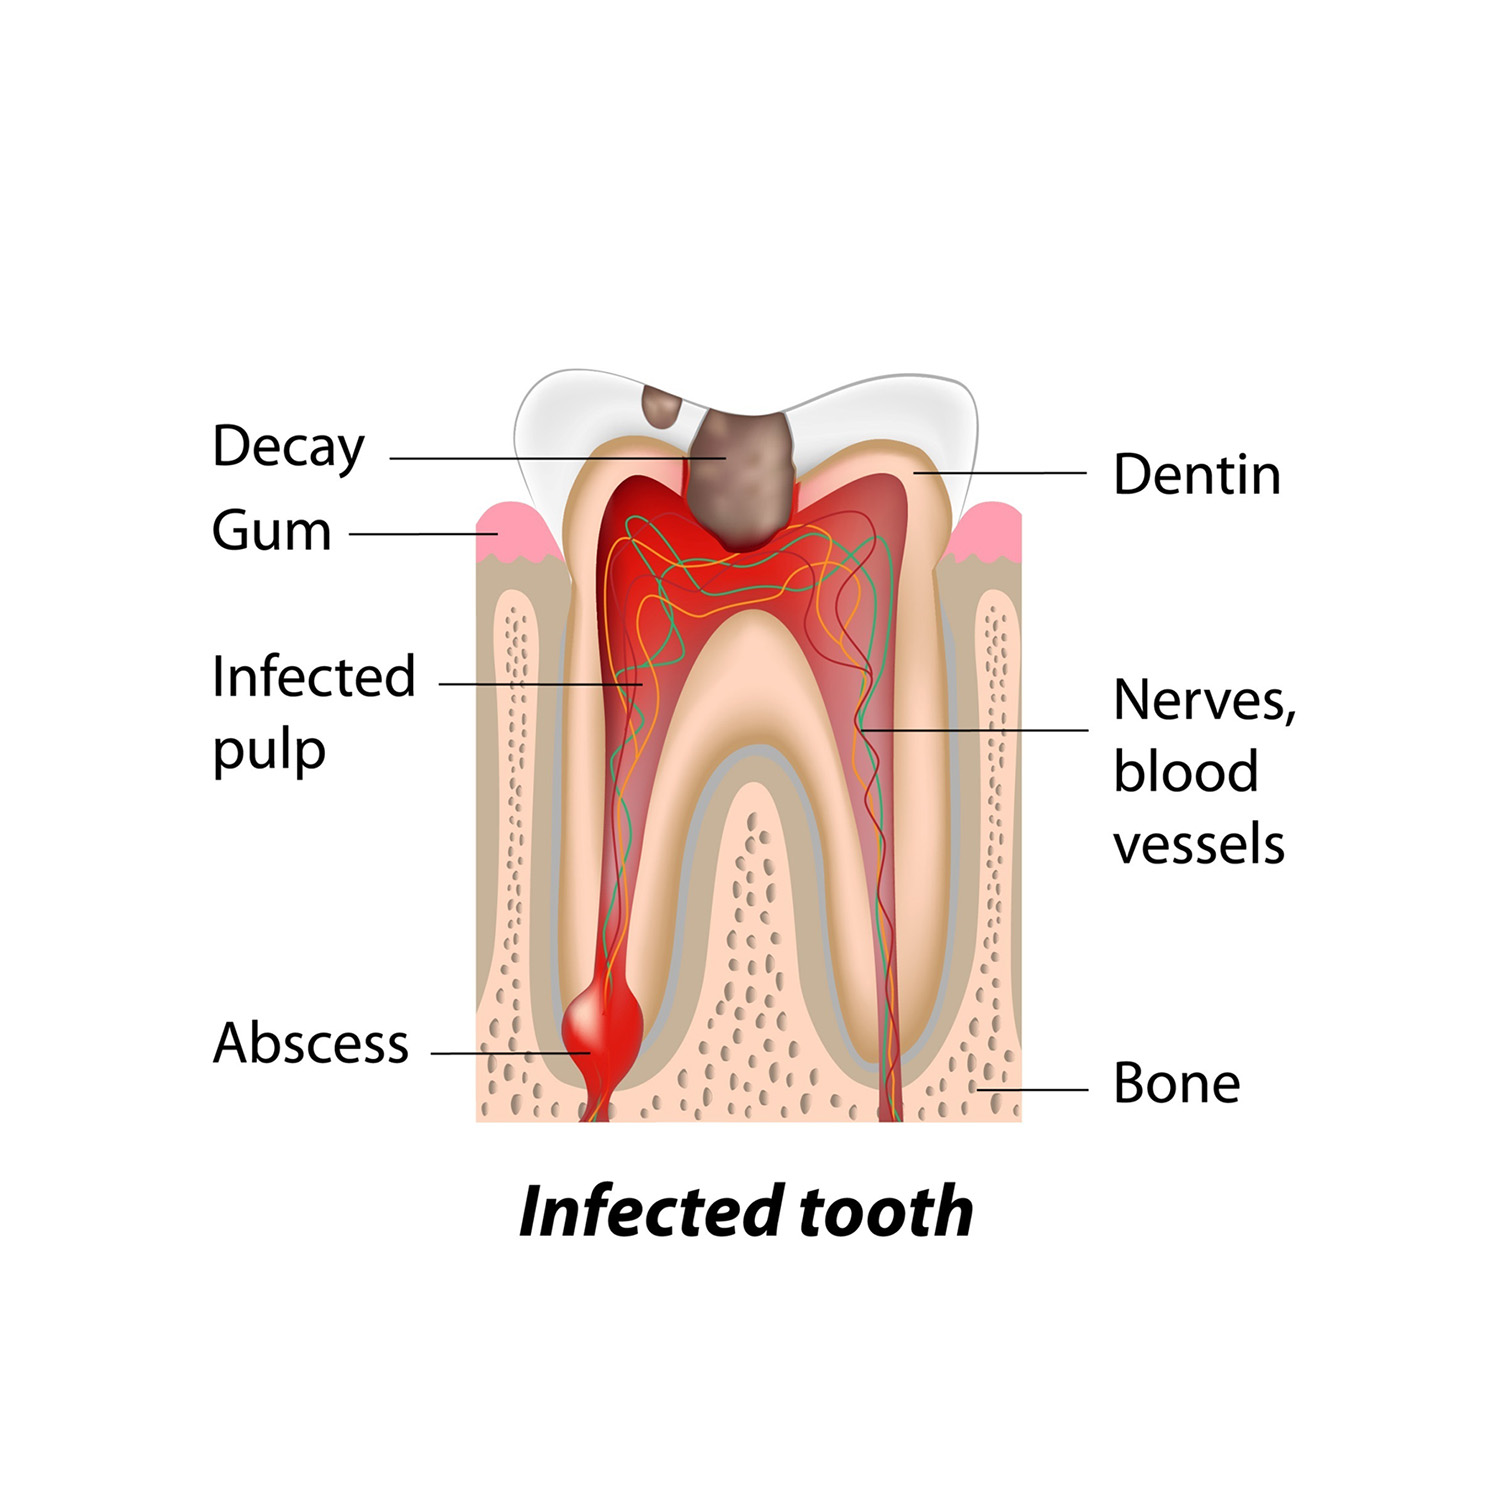

Every healthy tooth has a pulp chamber containing nerves and blood vessels. The pulp forms the roots during tooth development, provides sensation to the tooth when exposed to extreme temperatures, and signals when decay occurs.

However, not all cavities can be treated with just a filling. If decay or pre-existing damage is too deep, the pulp can become irreversibly inflamed and infected. Once the pulp is injured, the tooth begins to die, causing severe pain (toothache).

Over time, the infection can spread down the root, affecting surrounding structures. Swelling or pimple-like structures (sinus tracts) may develop on the gums. Other causes of pulp injury include: